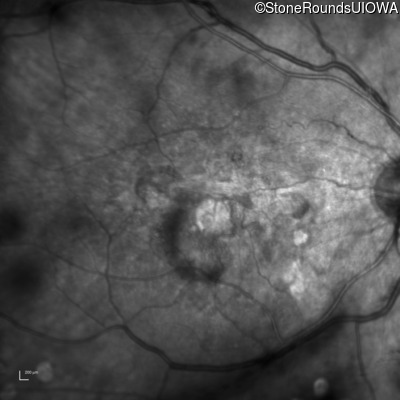

Malattia Leventinese (IIJ)

Malattia Leventinese (IIJ)

This 43 year old woman has experienced a gradual reduction in her central vision for the past 3 years.

| Malattia Leventinese | EFEMP1 | Arg345Trp CGG>TGG | AD |